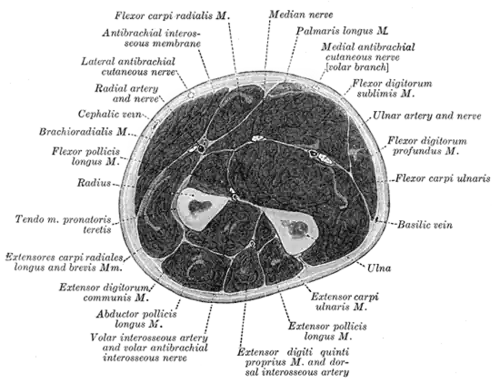

Querschnitt durch den Unterarm

Die Muskeln des Unterarmes werden ihrer Lage nach in zwei Gruppen unterteilt: Die Muskeln, die am lose hängenden Arm innen liegen und somit den Arm anbeugen (Flexoren) und die Muskeln, die außen liegen und den Arm strecken (Extensoren). Diese beiden Gruppen bestehen jeweils aus zwei einzelnen Schichten, die von der Körperoberfläche in die Tiefe gehen.

Unterarmmuskulatur

Beuger Strecker

Oberflächliche Schicht Tiefe Schicht Speichenseitige (radiale) Schicht Oberflächliche Schicht Tiefe Schicht

Musculus flexor carpi radialis Musculus pronator quadratus Musculus brachioradialis Musculus extensor carpi ulnaris Musculus abductor pollicis longus

Musculus flexor carpi ulnaris Musculus flexor pollicis longus Musculus extensor carpi radialis brevis Musculus extensor digitorum Musculus extensor pollicis brevis

Musculus flexor digitorum superficialis Musculus flexor digitorum profundus Musculus extensor carpi radialis longus Musculus extensor digiti minimi Musculus extensor pollicis longus

Musculus palmaris longus Musculus extensor indicis

Musculus pronator teres Musculus supinator